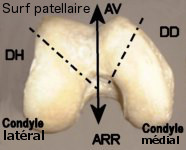

-

patellaire (old. trochlée fémorale)

avance plus du côté externe empêchant la luxation de la patella) La

joues qui se prolongent en ARR par les condyles fémoraux séparés à

plus long que le latéral. Trochlée et condyles sont séparés par 2

- sur la patella : la face

. Celle-ci est constituée de 2 champs séparés par une crête verticale

s'oppose à la trochlée fémorale